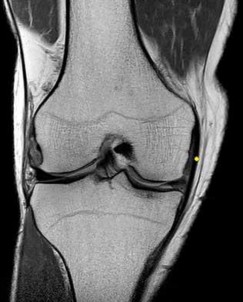

CLINICAL SITUATION FOR QUESTIONS 22 THROUGH 25

A 22-year-old man sustains an injury to his right knee in a motor vehicle collision. Figure 22a is the posterior stress radiograph of the involved knee, and Figure 22b is a selected MR image that identifies the injured structure.

The stress radiographs demonstrate posterior instability of the right knee in flexion. The MR images demonstrate injury to both the anterior and posterior cruciate ligament (PCL), with the stump identified with the arrow on the MR image (Figure 22b). The PCL has 2 functional bands. The anterolateral bundle originates from the roof of the intercondylar notch. It runs in a posterolateral direction onto the tibial crest between the posterior attachment of the medial and lateral menisci. During a double-bundled posterior ligament reconstruction, the

anterolateral bundle is tensioned with the knee in a position of mid flexion. The posteromedial bundle has a variable pattern of tension both in extension and in high flexion. Tensioning of the posteromedial bundle in extension may contribute to resistance against knee hyperextension.

The meniscofemoral ligaments are variably present. Although 93% of knees have been reported to have at least 1 meniscofemoral ligament present, both ligaments are simultaneously present in approximately 50% of knees. The ligament of Humphrey (anterior meniscofemoral ligament) and ligament of Wrisberg (posterior meniscofemoral ligament) are delineated by their anatomic relationship to the posterior cruciate.